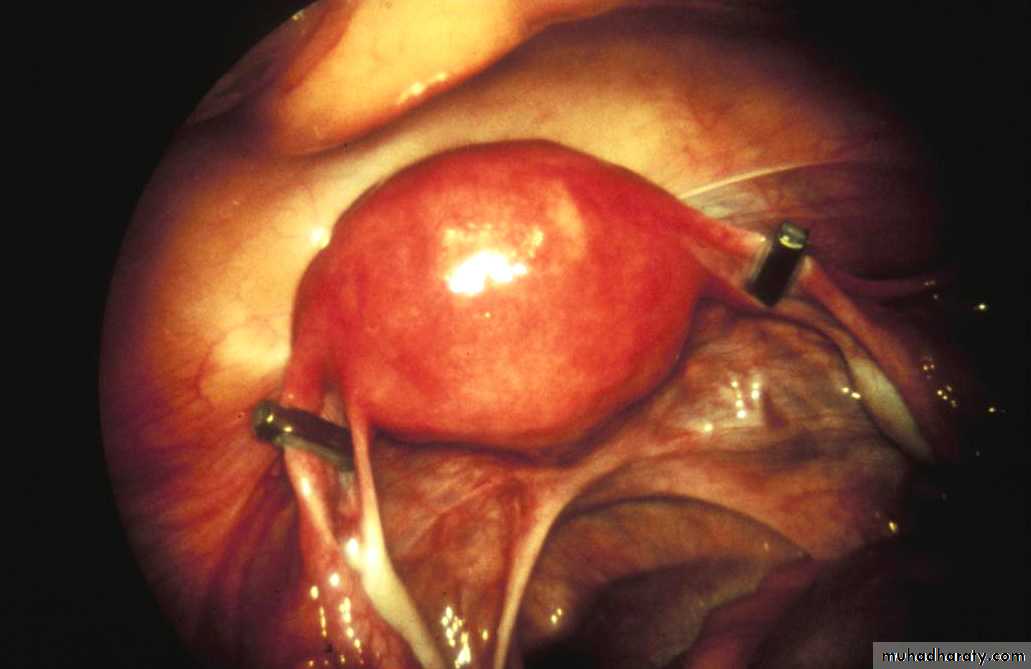

Pomeroy technique

• Incision – suprapubic and subumbilical• Isthmic portion is ligated twice

• Segment is then excised

Benefits

• Easy technique

• Highly effective

• Relatively inexpensive)

Tied

Cut

Final result